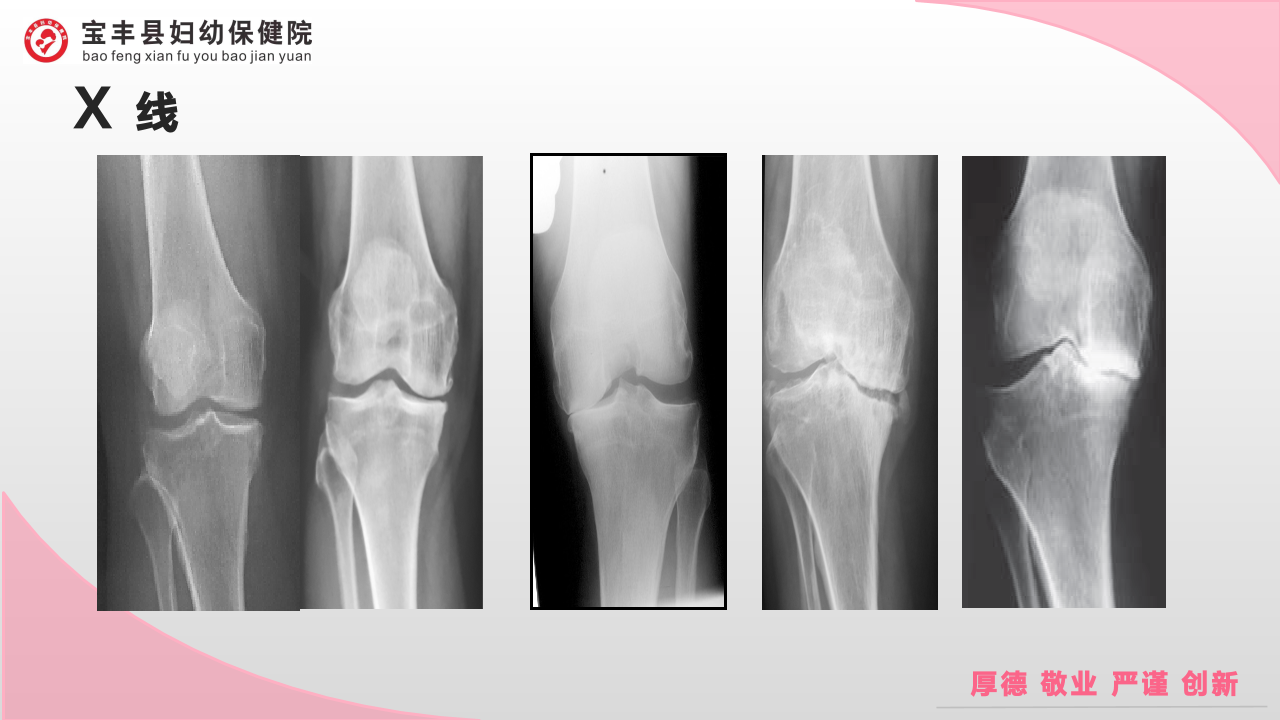

膝骨性关节炎的阶梯治疗